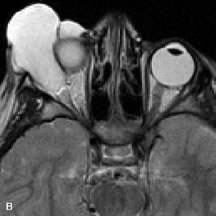

MRI is an excellent modality for demonstrating enlargement of the cavernous sinus and dilation of the superior ophthalmic vein in patients with high-flow carotid-cavernous fistulas (Fig. 14).37MRA may be helpful in the evaluation of the venous outflow pattern. The rapidly flowing blood in these vascular structures carries the excited protons out of the section before they can be imaged, resulting in their dark appearance.5 In low-flow dural arteriovenous malformations, MRA may help define the arterial feeding vessels.45

Fig. 14. Patient with Ehlers-Danlos syndrome who presented with abrupt onset of severe proptosis. A-C. Postcontrast fat-suppressed T1-weighted MR scans demonstrate marked proptosis and engorgement of the extraocular muscles and superior ophthalmic vein (arrows). D. T2-weighted scan through the cavernous sinus demonstrates enlargement and arterialized flow void within the right cavernous sinus (open arrow).